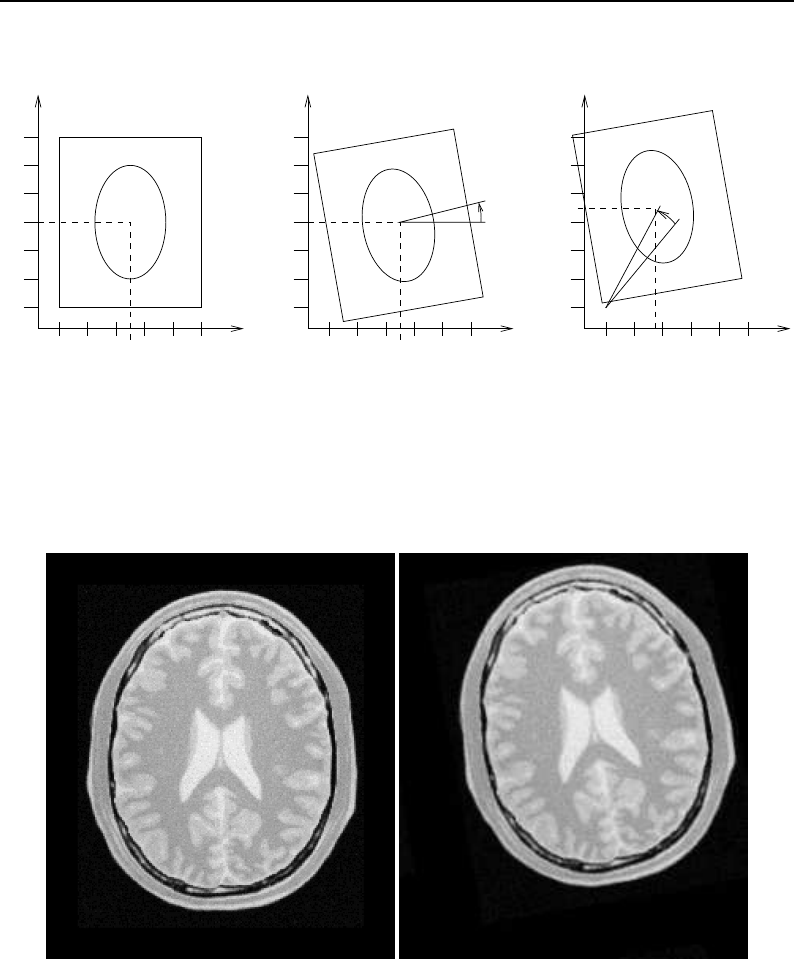

- Geometrical Representation

- Deformable Registration

- Demons Deformable Registration